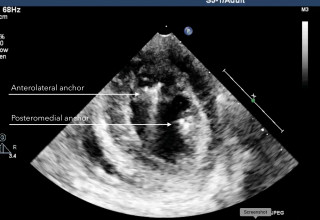

Schematic of the experimental setup. Vesalius anchors are deployed into opposing papillary muscles.

Echocardiographic images were obtained during the procedure and, subsequently, at seven, 30 and 180 days by Dr. Christopher Durkin, a cardiovascular anaesthesiologist, echocardiographer, and VCI's clinical advisor, who added, "Imaging at 180 days confirms the absence of mitral regurgitation and, more importantly, the absence of anchor migration, proving that VCI's anchors are acting exactly like the native chordae attachments."